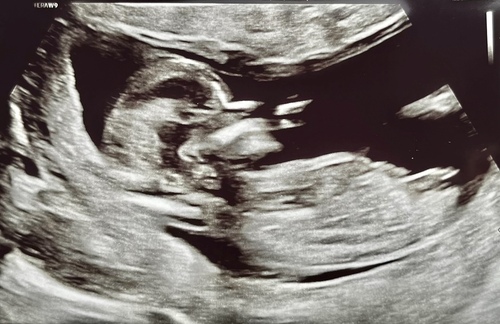

Hee allemaal, zojuist een echo gehad op 13+4. Ik weet niet zo goed of dit een goede foto is voor de nub.. iemand die een gokje kan wagen op basis hiervan? 🥰💖🩵

Meisje

Ik denk een meisje